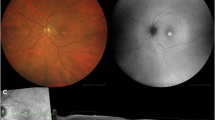

Recently, the VMD2 gene has been identified as the causative gene in juvenile-onset vitelliform macular dystrophy (Best disease), a central retinopathy primarily characterised by an impaired function of the retinal pigment epithelium. In this study we have further characterised the spectrum of VMD2 mutations in a series of 41 unrelated Best disease patients. Furthermore we expanded our analysis to include 32 unrelated patients with adult vitelliform macular dystrophy (AVMD) and 200 patients with age-related macular degeneration (AMD). Both AVMD and AMD share some phenotypic features with Best disease such as abnormal subretinal accumulation of lipofuscin material, progressive geographic atrophy and choroidal neovascularisation, and may be the consequence of a common pathogenic mechanism. In total, we have identified 23 distinct disease-associated mutations in Best disease and four different mutations in AVMD. Two of the mutations found in the AVMD patients were also seen in Best disease suggesting a considerable overlap in the aetiology of these two disorders. There were no mutations found in the AMD group. In addition, four frequent intragenic polymorphisms did not reveal allelic association of the VMD2 locus with AMD. These data exclude a direct role of VMD2 in the predisposition to AMD.

The pseudohypopyon stage in adult-onset foveomacular vitelliform dystrophy